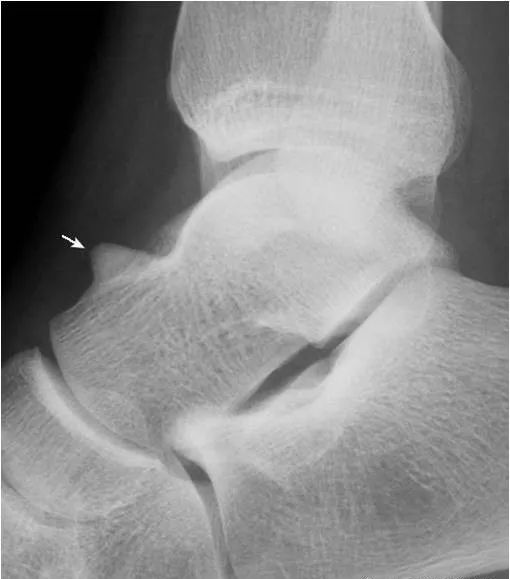

27.舟状骨粗隆撕脱骨折:

舟状骨粗隆后见游离小骨片(箭),与外胫骨及腓小骨的鉴别点在于骨片前缘模糊,无硬化缘,且与粗隆有较好的对合关系,同时邻近软组织明显肿胀(箭头)。